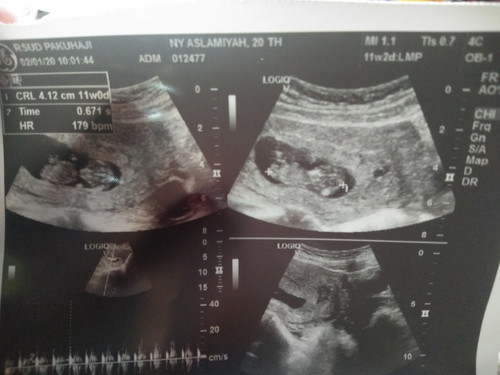

hasil usg

Hasil usg 11w alhamdulillah sehat dan sekarang udah jalan 4bln